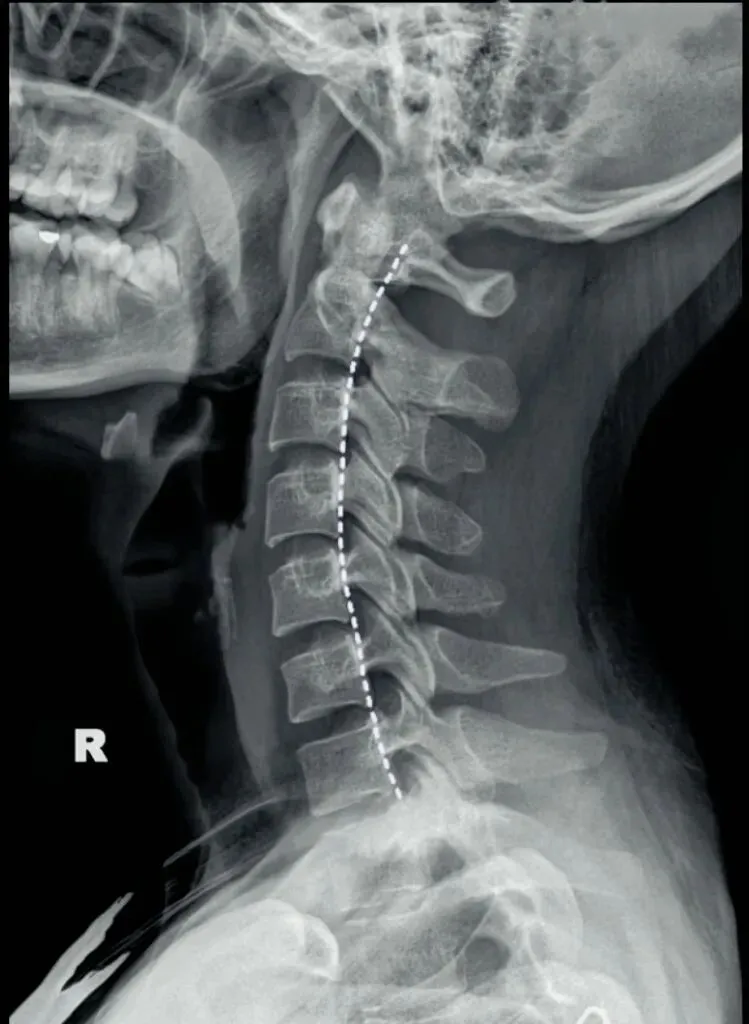

二弓指的是颈椎生理曲度,在颈椎侧位X线片中,正常生理状态下呈现向前凸出的弧形曲线,呈半C型前凸类似弓形,是人体脊柱生理曲度的重要组成部分。颈椎曲度变化能够反映颈椎整体功能的变化。

常见的颈椎曲度改变有曲度变直和曲度反曲。

颈椎生理曲度测量的方法多种多样,其中应用最广泛的测量方法是Borden法。从齿状突后上缘开始向下将每个椎体后缘相连成为一条弧线,然后从齿状突后上缘至C7椎体后下缘作一直线测量,两条线间最宽处的垂直横交线的距离即为颈椎生理曲度深度。

正常时,最宽处在C4椎体水平正常为12毫米,正负5毫米,小于7毫米为生理曲度变直,大于17毫米为生理曲度过度前屈,小于零时为生理曲度反曲。